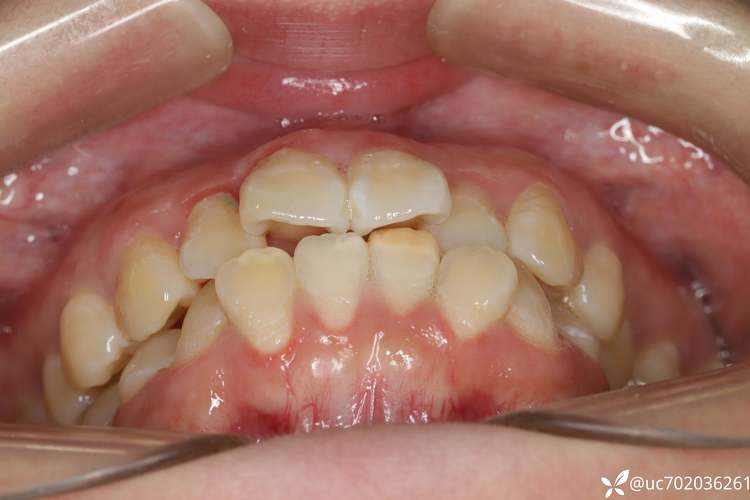

牙齿排列需满足“牙量与骨量的协调”——即牙齿总宽度与牙槽骨容纳空间是否匹配,当牙量大于骨量时,会出现牙齿拥挤、排列不齐;若骨量过大,则可能导致牙齿稀疏、前突等问题,拔牙矫治的核心目的,是通过减少牙量创造“空间”,实现以下目标:

解除拥挤:对于严重拥挤的牙齿,拔牙可提供移动空间,将扭转、错位的牙齿排齐,避免清洁困难导致的龋齿、牙周炎;

医生通过牙模测量“牙弓 Available Space”(牙弓可用空间)与“Required Space”(牙齿所需空间),计算差值以确定需拔牙的数量,通过头颅侧位片评估骨量、牙齿倾斜度、面部软组织轮廓,预测拔牙后的面型变化,对于轻度拥挤(2-4mm),通常可考虑邻面去釉或扩大牙弓;中度拥挤(4-8mm)可能需拔除1-2颗前磨牙;重度拥挤(>8mm)则可能需拔除2-4颗牙齿。